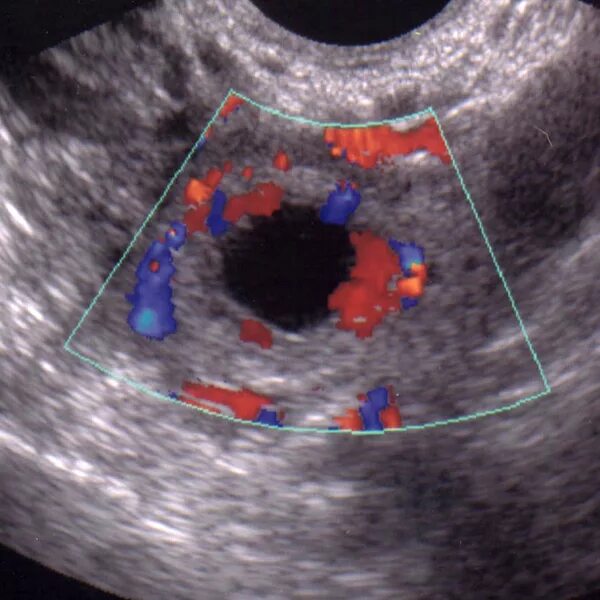

Ложное плодное яйцо на узи. ложное плодное яйцо по узи. внематочная беременность 6 недель узи. анэмбриония – пустое плодное яйцо.

Узи беременности на ранних. маточная беременность узи.

Узи матки на 5 неделе беременности. плодное яйцо на 5 неделе беременности. маточная беременность 6 недель. плодное яйцо по узи 5-6 недель.